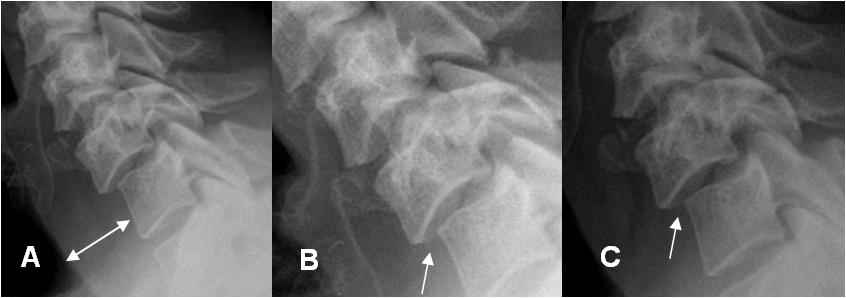

Fig 171. Proyecciones dinámicas.

A: Rx lateral. Anterolistesis G1 de C6, sobre C7 y aumento del espacio retroesofágico.

B: Rx lateral en flexión y C: Rx lateral en extensión. Desalineación que no se modifica, con las proyecciones dinámicas.

Fig 172. Falsa lesión ligamentaria.

A: Rx lateral en flexión y B: TAC reconstrucción sagital. Leve anterolistesis de C4, sobre C5.

C: RM sagital en T2. Adecuada alineación, sin signos de lesión ligamentaria.